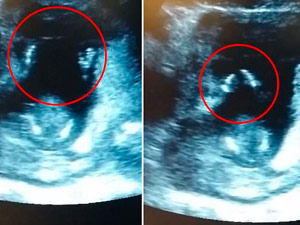

Đoạn clip ghi lại cảnh thai nhi 14 tuần tuổi vỗ tay theo nhạc khi người mẹ tên Jen Cardinal (Anh) và bác sĩ cùng ngân nga một bài hát dành cho thiếu nhi.

Sau khi chứng kiến cảnh tượng này, vị bác sĩ đã thốt lên đầy ngạc nhiên: "Thật tuyệt vời".